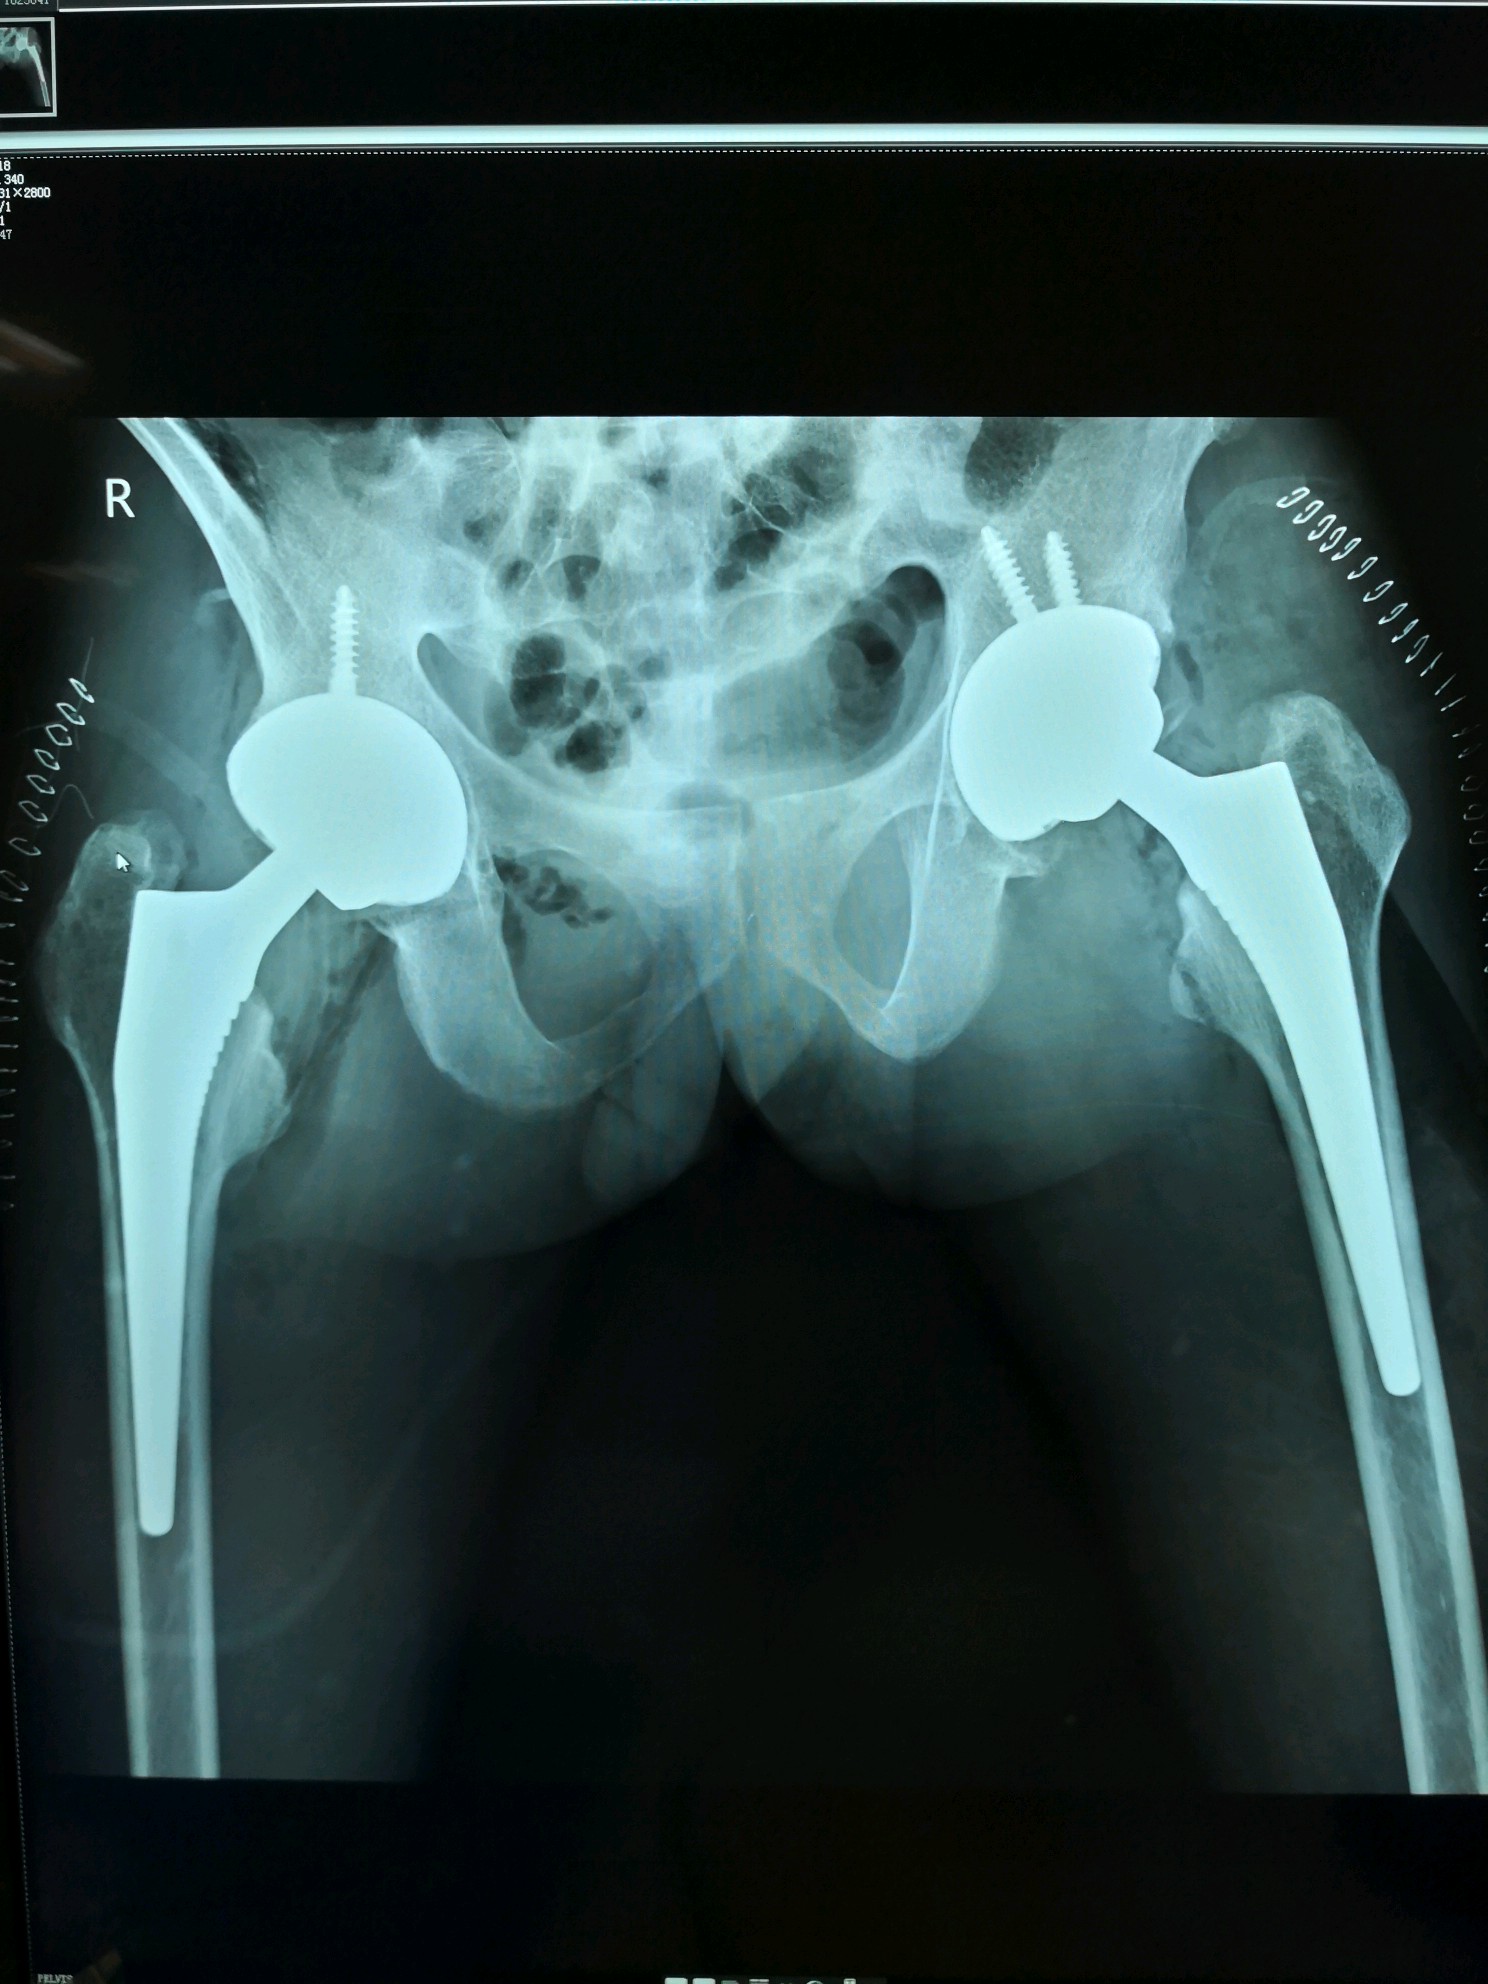

术后双髋正位片

图片发自160医生App

术后患者开始了正常的工作及生活。